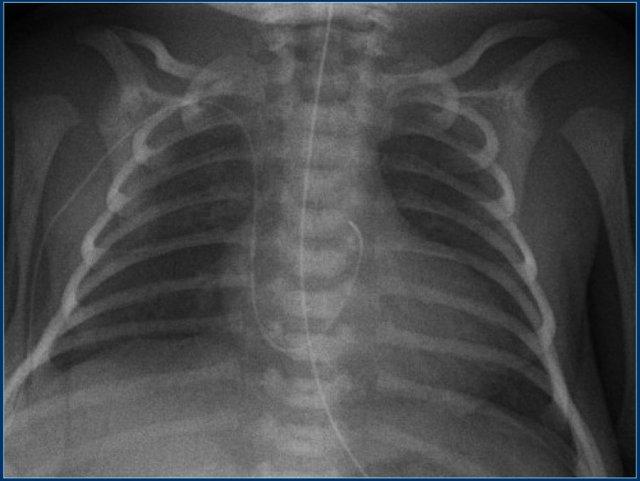

Các phát hiện bao gồm:

- PICC line đặt lạc chỗ, đi qua lỗ bầu dục còn thông vào nhĩ trái và tiếp theo vào tĩnh mạch phổi.